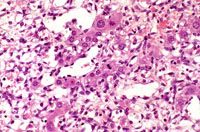

This Ito cell tumor is comprised of a mixture of stellate cells and mature adipocytes.